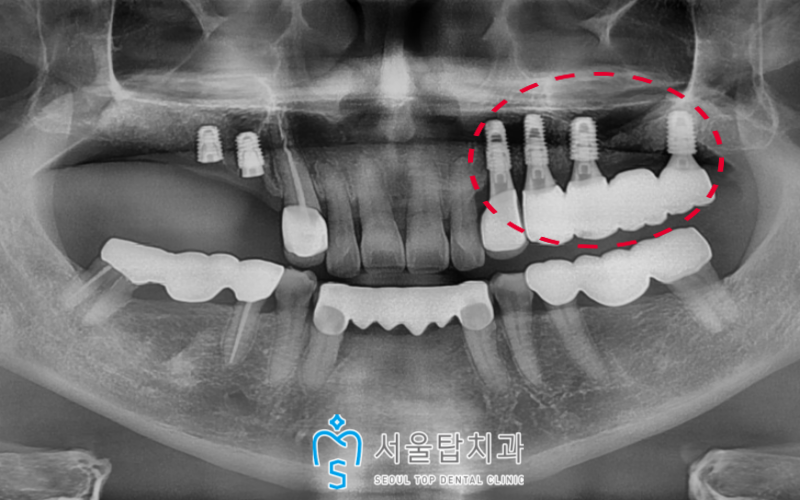

인공치근(픽스처)과

잇몸뼈가 단단해지기를

충분히 기다린 후

왼쪽 부위 먼저 임플란트 보철을

마무리해드렸습니다.

오른쪽 작은 어금니 자리 또한 (#14,15)

인공치근인 픽스처가

잇몸뼈에 단단하게 고정 된 것을 확인한 후

보철작업을 도와드렸습니다!

더불어 약 6개월이 지난 후

상악동 거상술 + 뼈이식을 진행하였던

큰 어금니 자리(#16,17)는

이제 임플란트를 식립할 수 있는

충분한 기반이 갖추어져

식립을 도와드렸답니다.